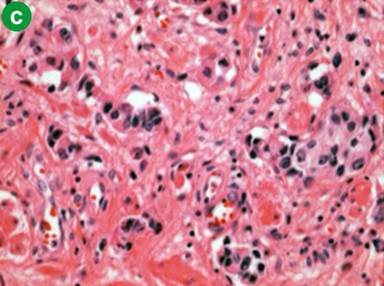

Following the diagnosis of autoimmune pancreatitis, screening CT images demonstrated pelvic lymph nodes that gradually increased in size (about 1.5 cm) and number. In June 2009, following CT detected an ill-enhanced hepatic tumor (Figure 3a). Endoscopic examinations denied upper and lower gastrointestinal tumors that could be the origin of hepatic tumor. Various candidates were considered, such as pseudotumor, cholangiocarcinoma, hepatocellular carcinoma, hepatic adenoma and metastasis of past bladder cancer. Percutaneous needle biopsy was performed to reach a final diagnosis. Histology of the biopsy tissue was urothelial carcinoma (Figure 3b), the same as in the bladder resected 5 years and 6 months previously (Figure 3c). The patient refused a second operation. Chemotherapy with gemcitabine was initially effective, but failed in one year, and metastasis developed in the adrenal gland, paranasal sinuses, and cervical vertebrae. Second line therapy by paclitaxel was not effective and the patient succumbed in January 2011.

Figure 3. Hepatic metastasis of the bladder cancer. a. CT showed an ill-enhanced, round-margined, tumor in the right lobe of the liver (arrow). b. Histology of percutaneous hepatic biopsy showed urothelial carcinoma, the same as that of urinary bladder resected 5 years and 6 months before (c.) (H&E, x100). |